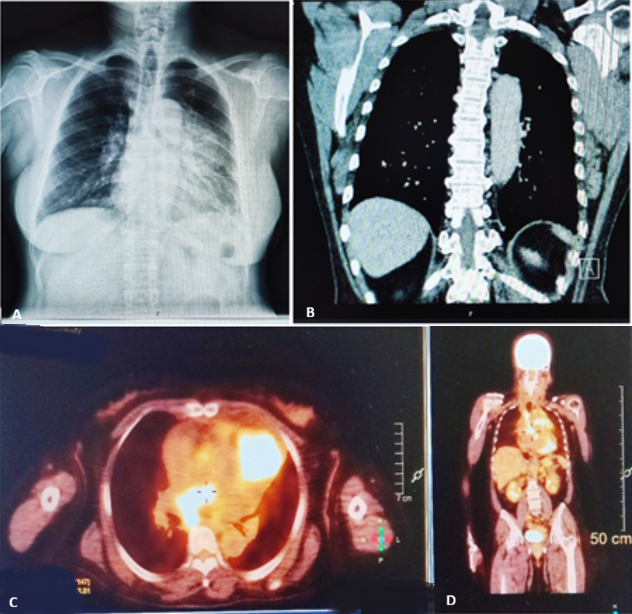

A 59-year-old woman with no prior history of malignancy presented with progressive chest pain, anorexia, fatigue, and unintentional weight loss. Chest radiography revealed a large anterior mediastinal opacity. Contrast-enhanced computed tomography (CT) demonstrated a heterogeneous anterior mediastinal mass measuring 73 × 67 × 62 mm, with deep calcifications and direct invasion of the pericardium and main pulmonary artery, associated with a 13 mm pericardial effusion. Enlarged mediastinal lymph nodes were observed in the prevascular, paratracheal, and subcarinal regions. Positron emission tomography (PET) showed intense hypermetabolic activity in the mediastinal mass and lymph nodes, as well as focal uptake in the cardiac region, increasing the suspicion of myocardial involvement. Pulmonary micronodules and adrenal lesions showed no significant metabolic activity. A percutaneous biopsy guided by computed tomography was performed, and histopathological examination revealed atypical polygonal epithelial cells and frequent mitoses. Immunohistochemical analysis was positive for CD5, CD117, p63, cytokeratin AE1/AE3, and CAM5.2, and negative for PAX8 and CK7, excluding pulmonary and thyroid origins. These findings established the diagnosis of advanced thymic epithelial carcinoma of the anterior mediastinum, with pericardial invasion and suspected cardiac involvement. Due to the advanced stage of the disease and poor prognosis, curative oncological treatment was not performed. The approach focused on palliative care, with pain control, treatment of dyspnea, and support for fatigue and functional decline. This case highlights the importance of multimodal imaging and immunohistochemistry in the diagnosis and staging of thymic carcinoma, and underscores the essential role of early palliative care in advanced mediastinal neoplasms.